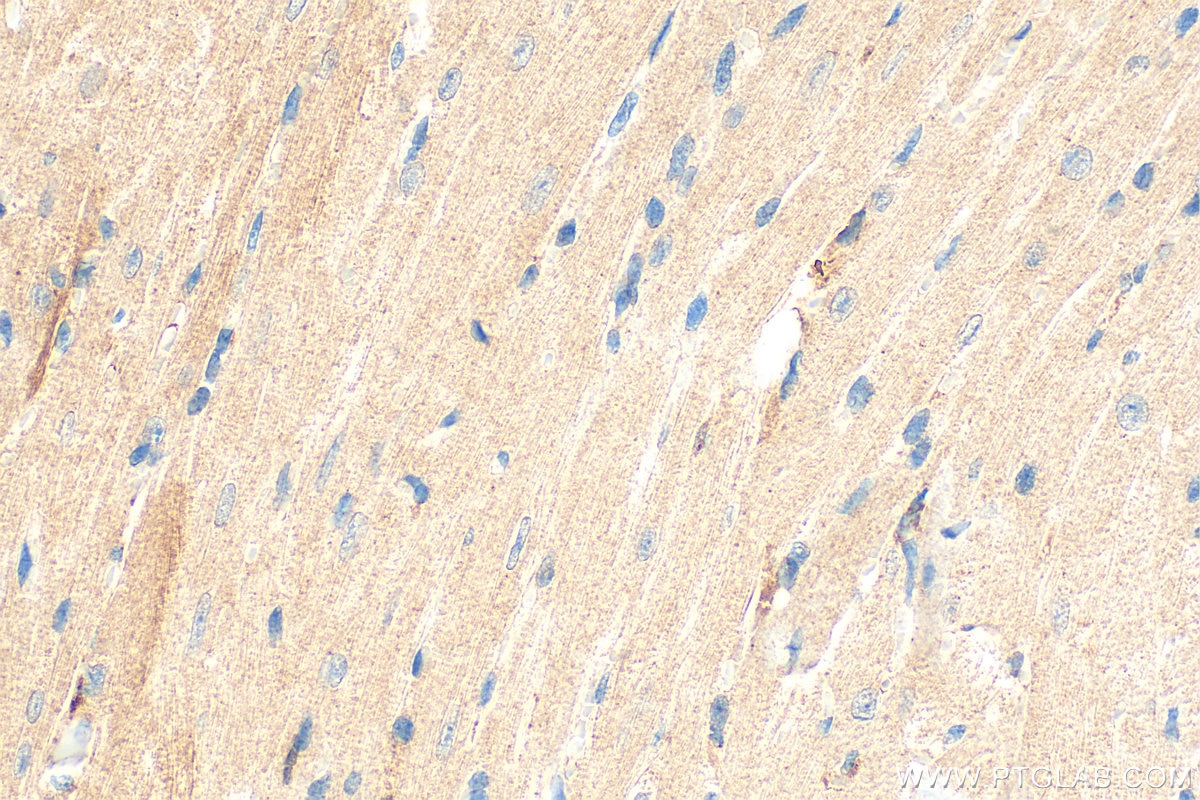

| Positive IHC detected in | human kidney tissue, mouse heart tissue Note: suggested antigen retrieval with TE buffer pH 9.0; (*) Alternatively, antigen retrieval may be performed with citrate buffer pH 6.0 |

20467-1-AP targets Spexin in IHC, IF-P, ELISA applications and shows reactivity with human, mouse samples.